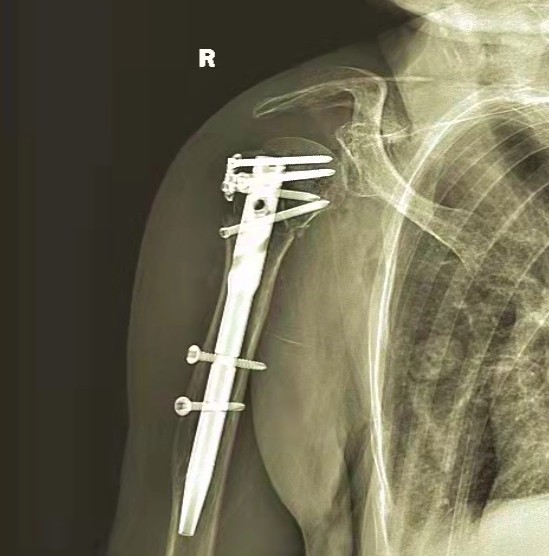

Rekonwalescencja pooperacyjna jest dobra w widoku rentgenowskim.